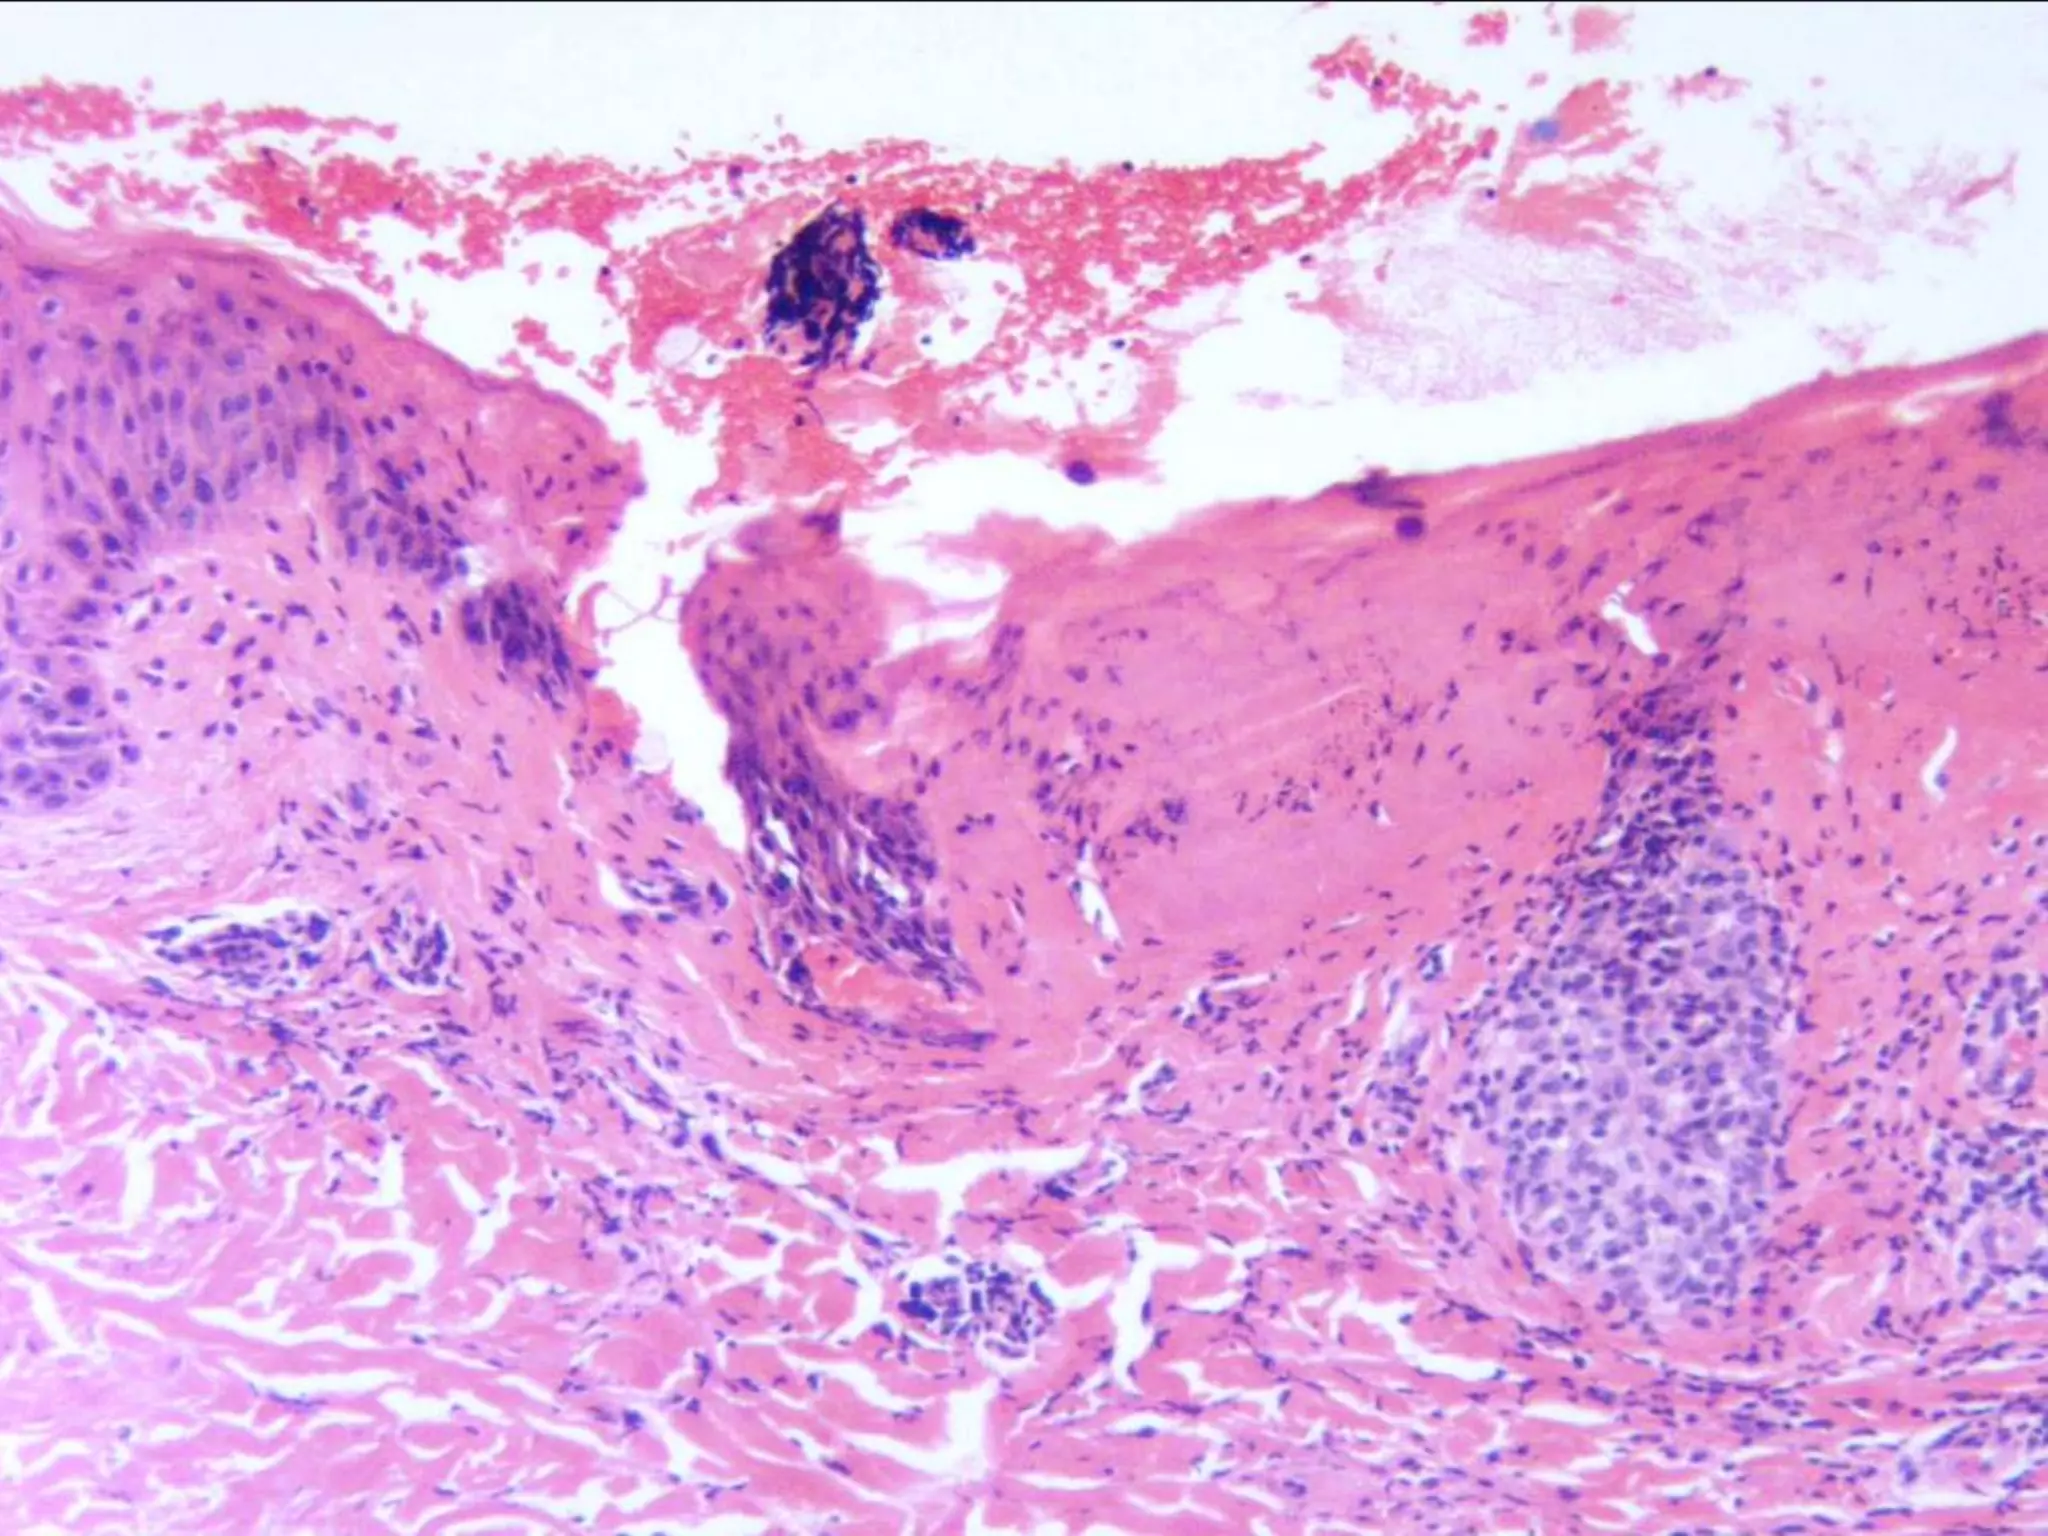

The document provides an overview of dermatopathology, including methods and techniques for skin biopsies such as shave, punch, and ellipse methods. It discusses key terms associated with dermatopathology, such as acantholysis and granulation tissue. Additionally, it references presentations by professionals in the field and essential dermatology resources.